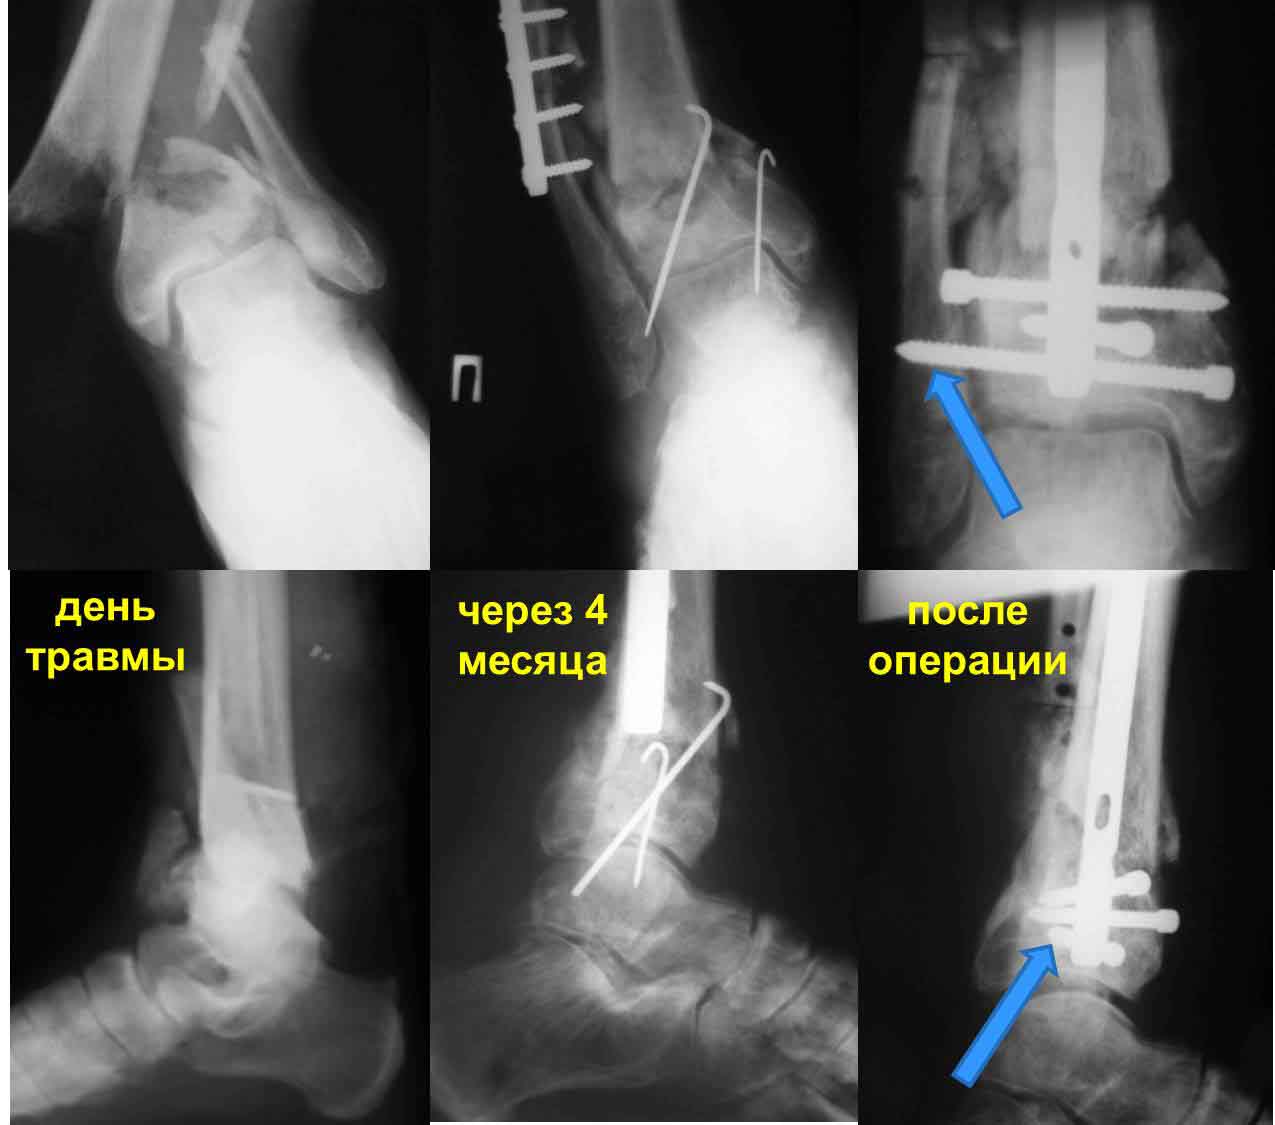

Уважаемые коллеги! Интересно ваше мнение по тактике лечения данной пациентки.Женщина 72 л соматически сохранная, умеренно полная, в мае прошлого года получила бытовую травму - открытый оскольчатый внутрисуставной перелом дистального метаэпифиза большеберцовой кости (Gustilo III-A) и поперечный перелом н/з малоберцовой кости со смещением отломков. Оперирована ургентно - открытая репозиция отломков малоберцовой кости, остеосинтез пластиной. ПХО раны голеностопного сустава, стабилизация отломков большеберцовой кости стержневым аппаратом. Репозиция отломков удовлетворительная (варус до 5 гр, рекурвация до 5 гр) - сильно за ней не гонялись, много осколков. В дальнейшем заживление ран первичное. Аппарат до 3 мес, затем гипсовая лонгета. Общий срок иммобилизации и разгрузки нижней конечности 4,5 мес - разрешена нагрузка после клинических и рентгенологических? признаков сращения. Последние 4 мес из поля зрения выпала, появилась сегодня. Беспокоят сильные боли при ходьбе, деформация голени, хромота. Р-контроль прилагается - варус 16 гр, рекурвация 35 гр (прошу прощения за качество снимков). Клинически варусно-рекурвационная деформация н/з голени, подвижность в н/з, боль. Движения в голеностопном суставе разгибание-сгибание 0/0/20. Трофика не нарушена, рубец области медиальной лодыжки плотный, спаян с подлежащими тканями. Больная хочет ходить без боли на ровной ноге (что вполне естественно). Возникает вопрос - как этого добиться? Удаление металлоконструкций, остеотомия малоберцовой на мой взгляд не обсуждаются - выполняются при любом из выбранных методов лечения (далее как мне видится в порядке предпочтения): - коррекция деформации аппаратом Илизарова с последующим БИОС ретроградным стержнем типа T2 AAN или аналогами (читал за и против данного метода, но по моему он единственный обеспечит больной раннюю нагрузку и стабильность пусть даже ценой потери ГСС (который и так уже потерян ИМХО) и ПТС). -коррекция деформации аппаратом Илизарова с оставлением этой фиксации как окончательной (необходимо ли выполнение свободной костной пластики). -открытая репозиция, остеосинтез LCP с костной пластикой. Данный метод на мой взгляд не позволит добиться хорошей стабильности, учитывая небольшой дистальный отломок и пороз кости (уже при первой операции обращала на себя "пустота" метаэпифиза), будет сопряжен с дополнительной иммобилизацией, как следствием потерей функции голеностопного сустава, невозможностью ранней нагрузки конечности. Кроме того, наиболее травматичное вмешательство, а м/ткани этой области скомпрометированы первичной травмой - как пойдет заживление. Таково мое видение проблемы. Женщине очень хочется помочь, поэтому буду рад выслушать все мнения, доводы "за" и "против" какого-то метода, другую тактику.

Уважаемый Антон! Видимо, Ваша пациентка повторно травмировала ногу, т.к. произошел повторный перелом малоберцовой кости и угловая деформация на уровне верхнего винта. К тому времени костная мозоль была еще слаба, и метаэпифиз б/берцовой кости "съехал" кпереди. Что делать? Сначала диагноз: неправильно сросшийся перелом метаэпифиза большеберцовой и н/3 малоберцовой костей, рекурвационная деформация. Из диагноза вытекает тактика: корригирующая остеотомия обеих костей, повторный остеосинтез. Остеотомию большеберцовой кости следует проводить на уровне верхнего края дистального отломка по профильному снимку, поперечно, малоберцовой кости - на уровне верхнего винта. После остеотомии следует совместить оси проксимального отломка и таранной кости, устранить угловую деформацию (она разная у обеих костей). Если останутся щелевидные дефекты (спереди), заполнить их аутокостью. Остеосинтез лучше проводить пластиной с угловой стабильностью "лист клевера", малоберцовой - 1/3 трубчатой (можно ту же пластину поднять на 2 отверстия) При расположении пластины по передней поверхности б/берцовой кости не забыть спилить и сровнять нижнюю часть пластины. Можно располагать и снутри, в этом случае после остеотомии и репозиции будет необходима краевая резекция дистального фрагмента, т.к. он будет выступать в виде ступени кнутри, эту же кость можно использовать для пластики. Возможна фиксация в Аппарате Илизарова - менее предпочтительный вариант. По доступам не могу советовать, но если возможно - передний дугообразный классический для большеберцовой и наружный для м/берцовой. Открывать кожу шире, для этого продлить доступ дистальнее внутренней лодыжки.

Частота ложных суставов и повторных смещений костных отломков после оперативной стабилизации переломов пилона доходит до 30%. Каждый, кто занимается лечением таких повреждений, наверняка сталкивался с такими осложнениями. Однако лечить такие осложнения в моральном, да и в оперативном плане проще, чем свежие переломы пилона (особенно Ruedi III), поскольку к этому времени становится более или менее понятной судьба голеностопного сустава. Если в достаточной мере владеете блокированным остеосинтезом, то самым оптимальным вариантом, с моей точки зрения, будет следующий. С переднемедиального и латерального доступов выполнить поперечную остеотомию большеберцовой и малоберцовой костей в плоскости параллельной плоскости голеностопного сустава на расстоянии около 3 см от самого сустава. Это минимальное расстояние, которое позволит расположить три блокирующих винта стержня. Важен выбор самого стержня. В данном случае больше всего подходит стержень ChM, имеющий на дистальном конце помимо отверстий в сагиттальной и фронтальной плоскостях и отверстия под углом в 45 градусов, причём на минимальном расстоянии друг от друга. Остетомию и последующую репозицию костных отломков мы выполняем в репозиционном спицевом аппарате. Стержень антеградный. В данном случае не вижу никаких оснований в применении ретроградного стержня, проходящего через здоровый подтаранный и через голеностопный сустав с его до конца неопределённой функцией. Образовавшийся дефект по переднемедиальной поверхности должен быть заполнен костным трансплантатом. Пример похожего случая из нашей практики - в приложенном файле.

Это результат не повторной травмы, а типичной ошибки леченного без учета характера травмы перелома пилона . При переломах пилона укорочение конечности происходит за счет компрессии дистального метафизарного фрагмента. Поэтому при лечении необходимо замещение пустоты структурным костным графтом с нейтрализацией медиальной (Butress) пластиной. Иначе фиксированная малоберцовая после первых шагов поведет большеберцовую в варус.

Циркулярные аппараты типа Илизарова из-за равномерной нейтрализации с двух сторон могут удержать короткий дистальный сегмент до конца лечения, но односторонние наружные фиксаторы не смогут создать адекватную фиксацию. Поэтому наружные фиксаторы при свежих переломах пилона применяются в основном как временная дистрагирующая сила, а окончательную фиксацию необходимо провести после улучшения мягких тканей.